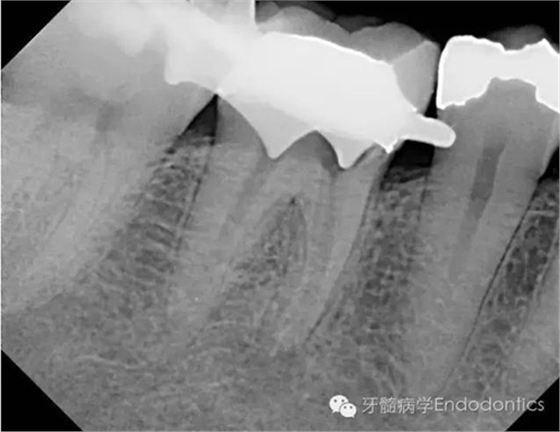

我決定對(duì)患牙行一次性根管再治療。我成功的取出了一根斷針和三根(其中兩根超出根尖)Thermofil(固核載體)。對(duì)所有根管進(jìn)行徹底的清理、成形,干燥后使用熱牙膠垂直加壓技術(shù)完成充填。

圖4.取出根管內(nèi)充填物后拍攝的X線片